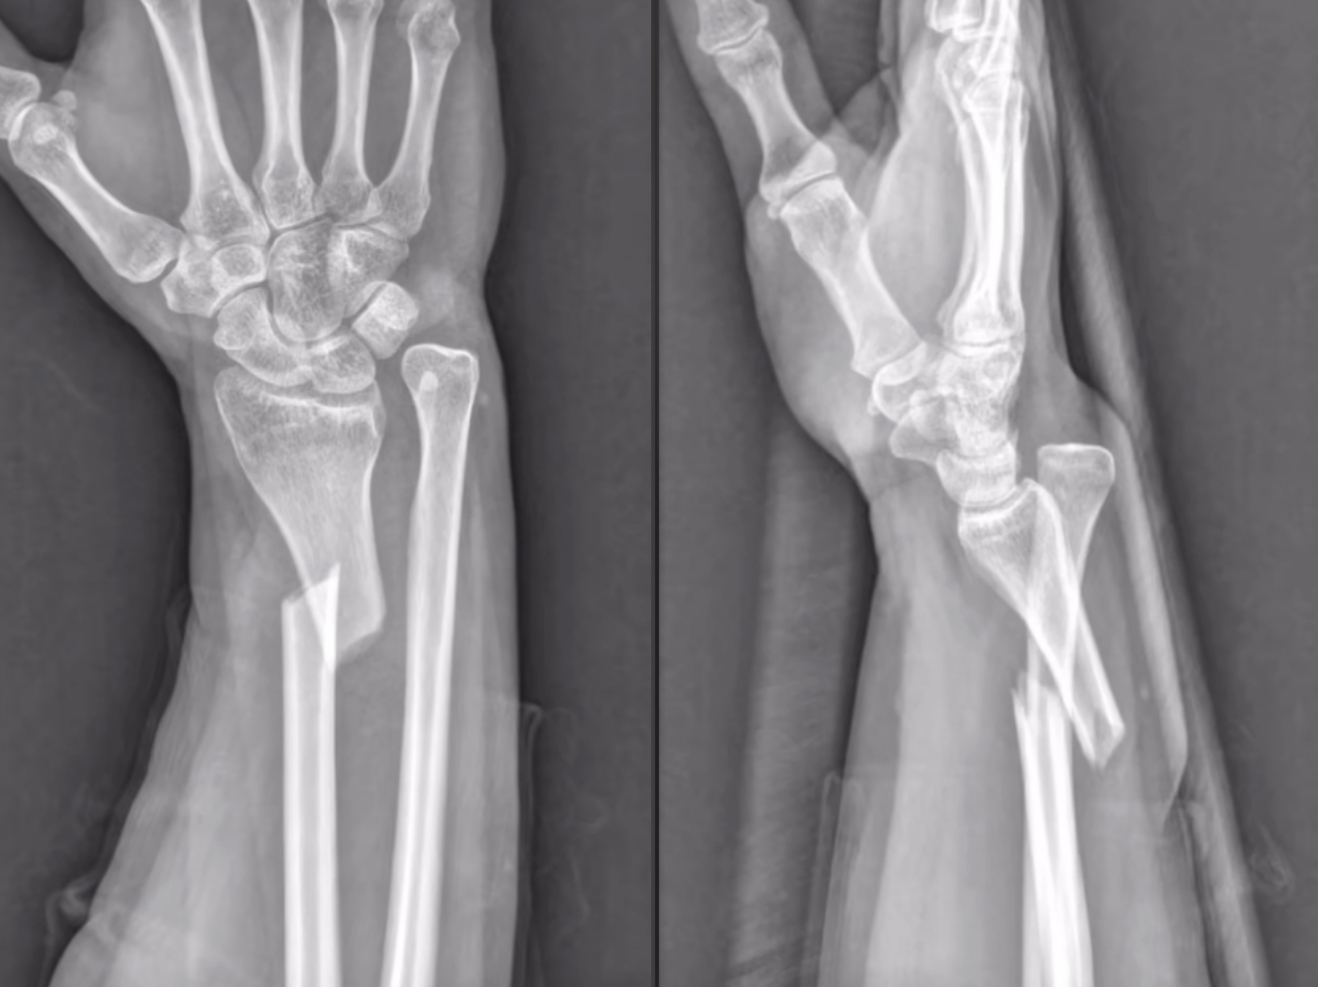

尺橈骨遠(yuǎn)端骨折復(fù)位前 尺橈骨遠(yuǎn)端骨折復(fù)位后